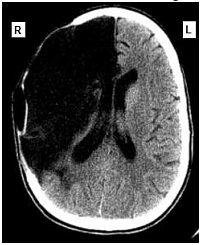

Uma mulher de sessenta e dois anos de idade foi levada pelo acompanhante ao atendimento médico de um hospital, às 7 horas e 30 minutos da manhã. O acompanhante relatou que a paciente tinha sofrido uma queda no banheiro de sua residência enquanto tomava banho, às 6 horas da manhã, e que ele a havia encontrado minutos depois. A paciente não conseguia mover o braço e a perna esquerdos, falava de forma lenta e arrastada, mas com sentido lógico. No exame clínico, foram observadas pressão arterial de 160 mmHg × 95 mmHg, ausculta cardíaca com ritmo cardíaco irregularmente irregular e frequência cardíaca de 98 bpm, sem sopros. A paciente estava com lentidão para responder a questionamentos, apresentava pupilas isocóricas e fotorreagentes, diminuição da sensibilidade dolorosa no lado esquerdo da face, paralisia facial central, hemiparesia flácida do hemicorpo esquerdo (mais acentuada nos membros superiores), reflexos profundos mais acentuados à esquerda e sinal de Babinski à esquerda. No eletrocardiograma realizado foram detectados ritmo de fibrilação atrial, com frequência ventricular média de 100 spm, SÂQRS = -30º, sinais de sobrecarga ventricular esquerda e alterações difusas e secundárias da repolarização ventricular. A tomografia computadorizada do crânio, sem contraste, realizada na paciente, apresentou o resultado mostrado a seguir.

Internet:<www.emedicinehealth.com> (com modificações).

Com relação a esse caso clínico, julgue o item seguinte.

Nesse caso, o uso de medicação trombolítica é contraindicado por ter ultrapassado o tempo da janela terapêutica.

O caso clínico em questão permite concluir a existência de correlação causal entre os achados eletrocardiográficos observados nessa paciente e a situação clínica neurológica observada.